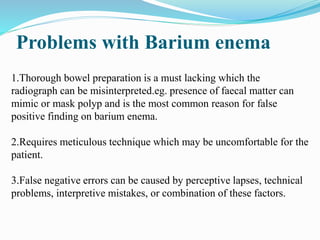

This document discusses colorectal polyps. It defines polyps and describes their types, including neoplastic and non-neoplastic polyps. It discusses adenomatous polyps in depth, noting their malignant potential increases with size over 1cm and villous architecture. Radiological diagnostic methods for polyps including single and double contrast barium enema and CT colonography are explained. The document provides an overview of polyp pathogenesis and genetic syndromes like FAP that increase cancer risk.